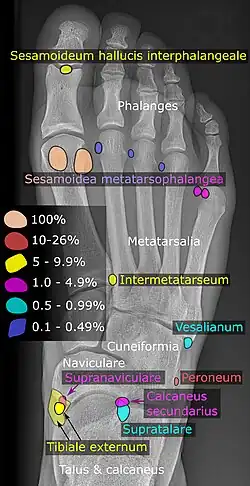

Insbesondere an den Fußwurzelknochen können eine Reihe von akzessorischen Fußwurzelknochen beobachtet werden. Sie sind teilweise weitverbreitet und in vielen Fällen symptomlos. Meist handelt es sich um Zufallsbefunde bei einer Röntgenuntersuchung. Das Os tibiale externum ist beispielsweise bei etwa einem Fünftel aller Erwachsenen vorhanden.[11] Das Os trigonum kommt bei 3–15 % der Erwachsenen vor.